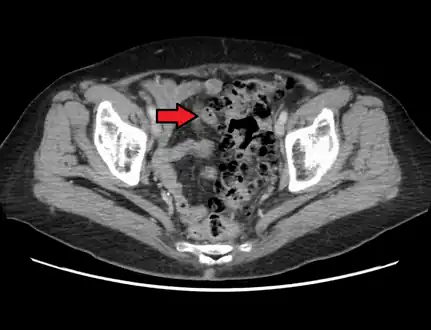

CT scan showing extensive diverticulosis of the sigmoid colon

Diverticular disease

Diverticulosis is defined by the presence of multiple pouches (diverticula) in the colon.[22] In people without symptoms, these are usually found incidentally during other investigations.

While a good history is often sufficient to form a diagnosis of diverticulosis or diverticulitis, it is important to confirm the diagnosis and rule out other pathology (notably colorectal cancer) and complications.

- Contrast CT is the investigation of choice in acute episodes of diverticulitis and where complications exist.